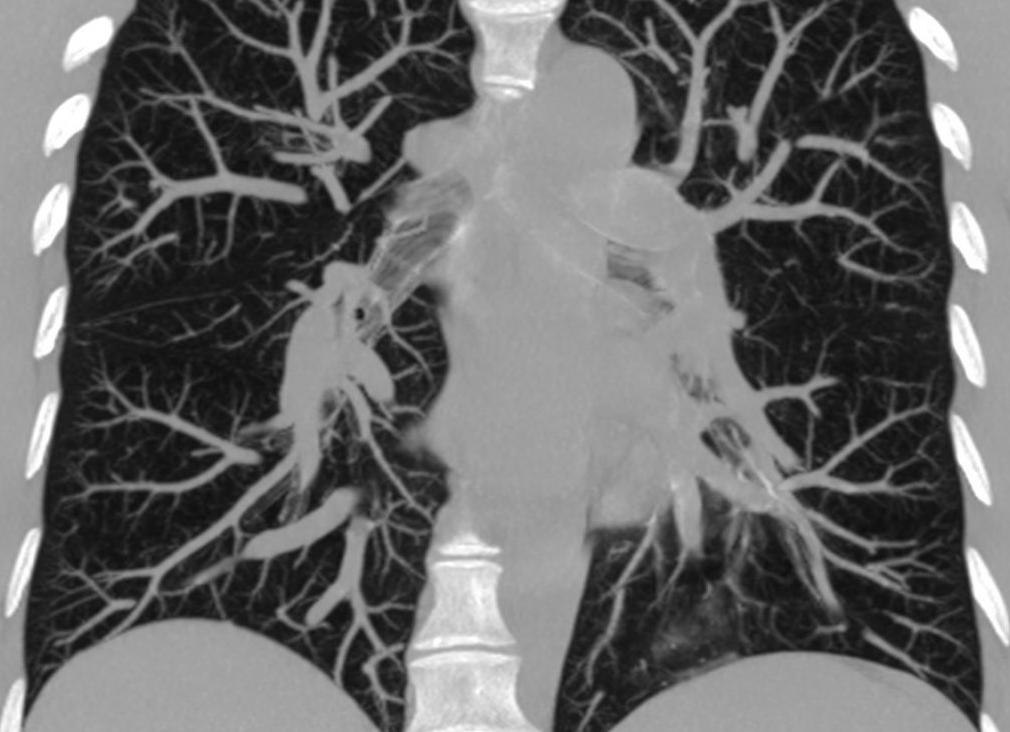

КТ грудной клетки помогает исследовать легкие и бронхи, а также аорты и артерии.

Компьютерная томография органов грудной полости – это метод послойного сканирования тканей с помощью рентгеновских лучей. Аппарат устроен таким образом, что источником лучей служит спиральный контур, внутри которого расположен стол для пациента. Томограф производит серию снимков органов под разным углом с отдельных точек. Компьютерная программа, обрабатывая информацию, моделирует объёмное трёхмерное изображение.

Толщина среза снимков составляет всего 1 мм, что увеличивает точность диагностики. К тому же врач поворачивает компьютерный снимок в нужной проекции, приблизив изображение для детального изучения. КТ органов грудной клетки выявляет патологию жизненно важных органов – сердца и лёгких.

Серия КТ снимков грудной клетки

Компьютерная томография органов грудной клетки позволяет оценить состояние органов благодаря послойному изображению трехмерного формата.

Компьютерная томография органов грудной клетки позволяет оценить состояние органов благодаря послойному изображению трехмерного формата. В этом – ее основное отличие от других диагностических способов. Толщина одного слоя может составлять 1 миллиметр – а значит, будут замечены даже очень небольшие патологии.